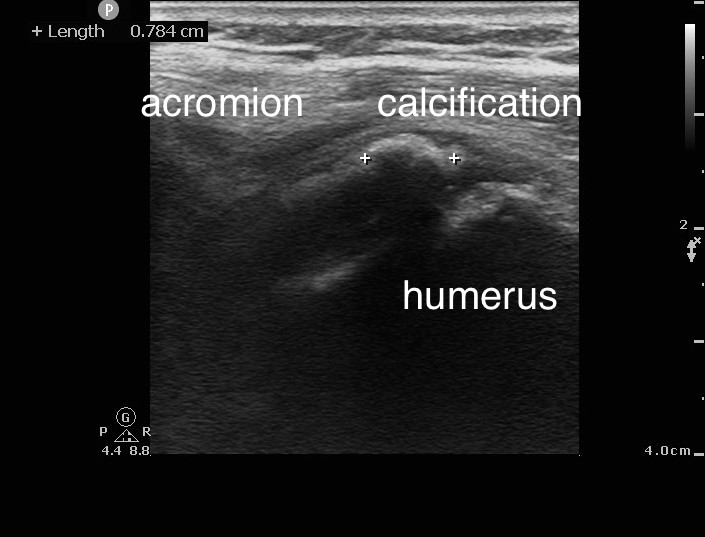

個案56歲女性,右肩外側疼痛4天。無明顯紅腫。生命徵象穩定,急診就診前一天有些微發燒,理學檢查右肩外側一處明顯壓痛,右上臂無法上抬。超音波影像上看到肩關節少量積液(影片8、影片9),但主要疼痛部位在棘上肌腱上的鈣化病變 (圖片6、圖片7)。在超音波導引下我們為該患者進行治療 (影片10),患部疼痛立即得到緩解後自急診出院,安排後續復健科追蹤。

圖片656歲女性,右肩疼痛數日。肩部X光可見鈣化點

圖片756歲女性,右肩疼痛數日。超音波可見棘上肌腱上鈣化病變